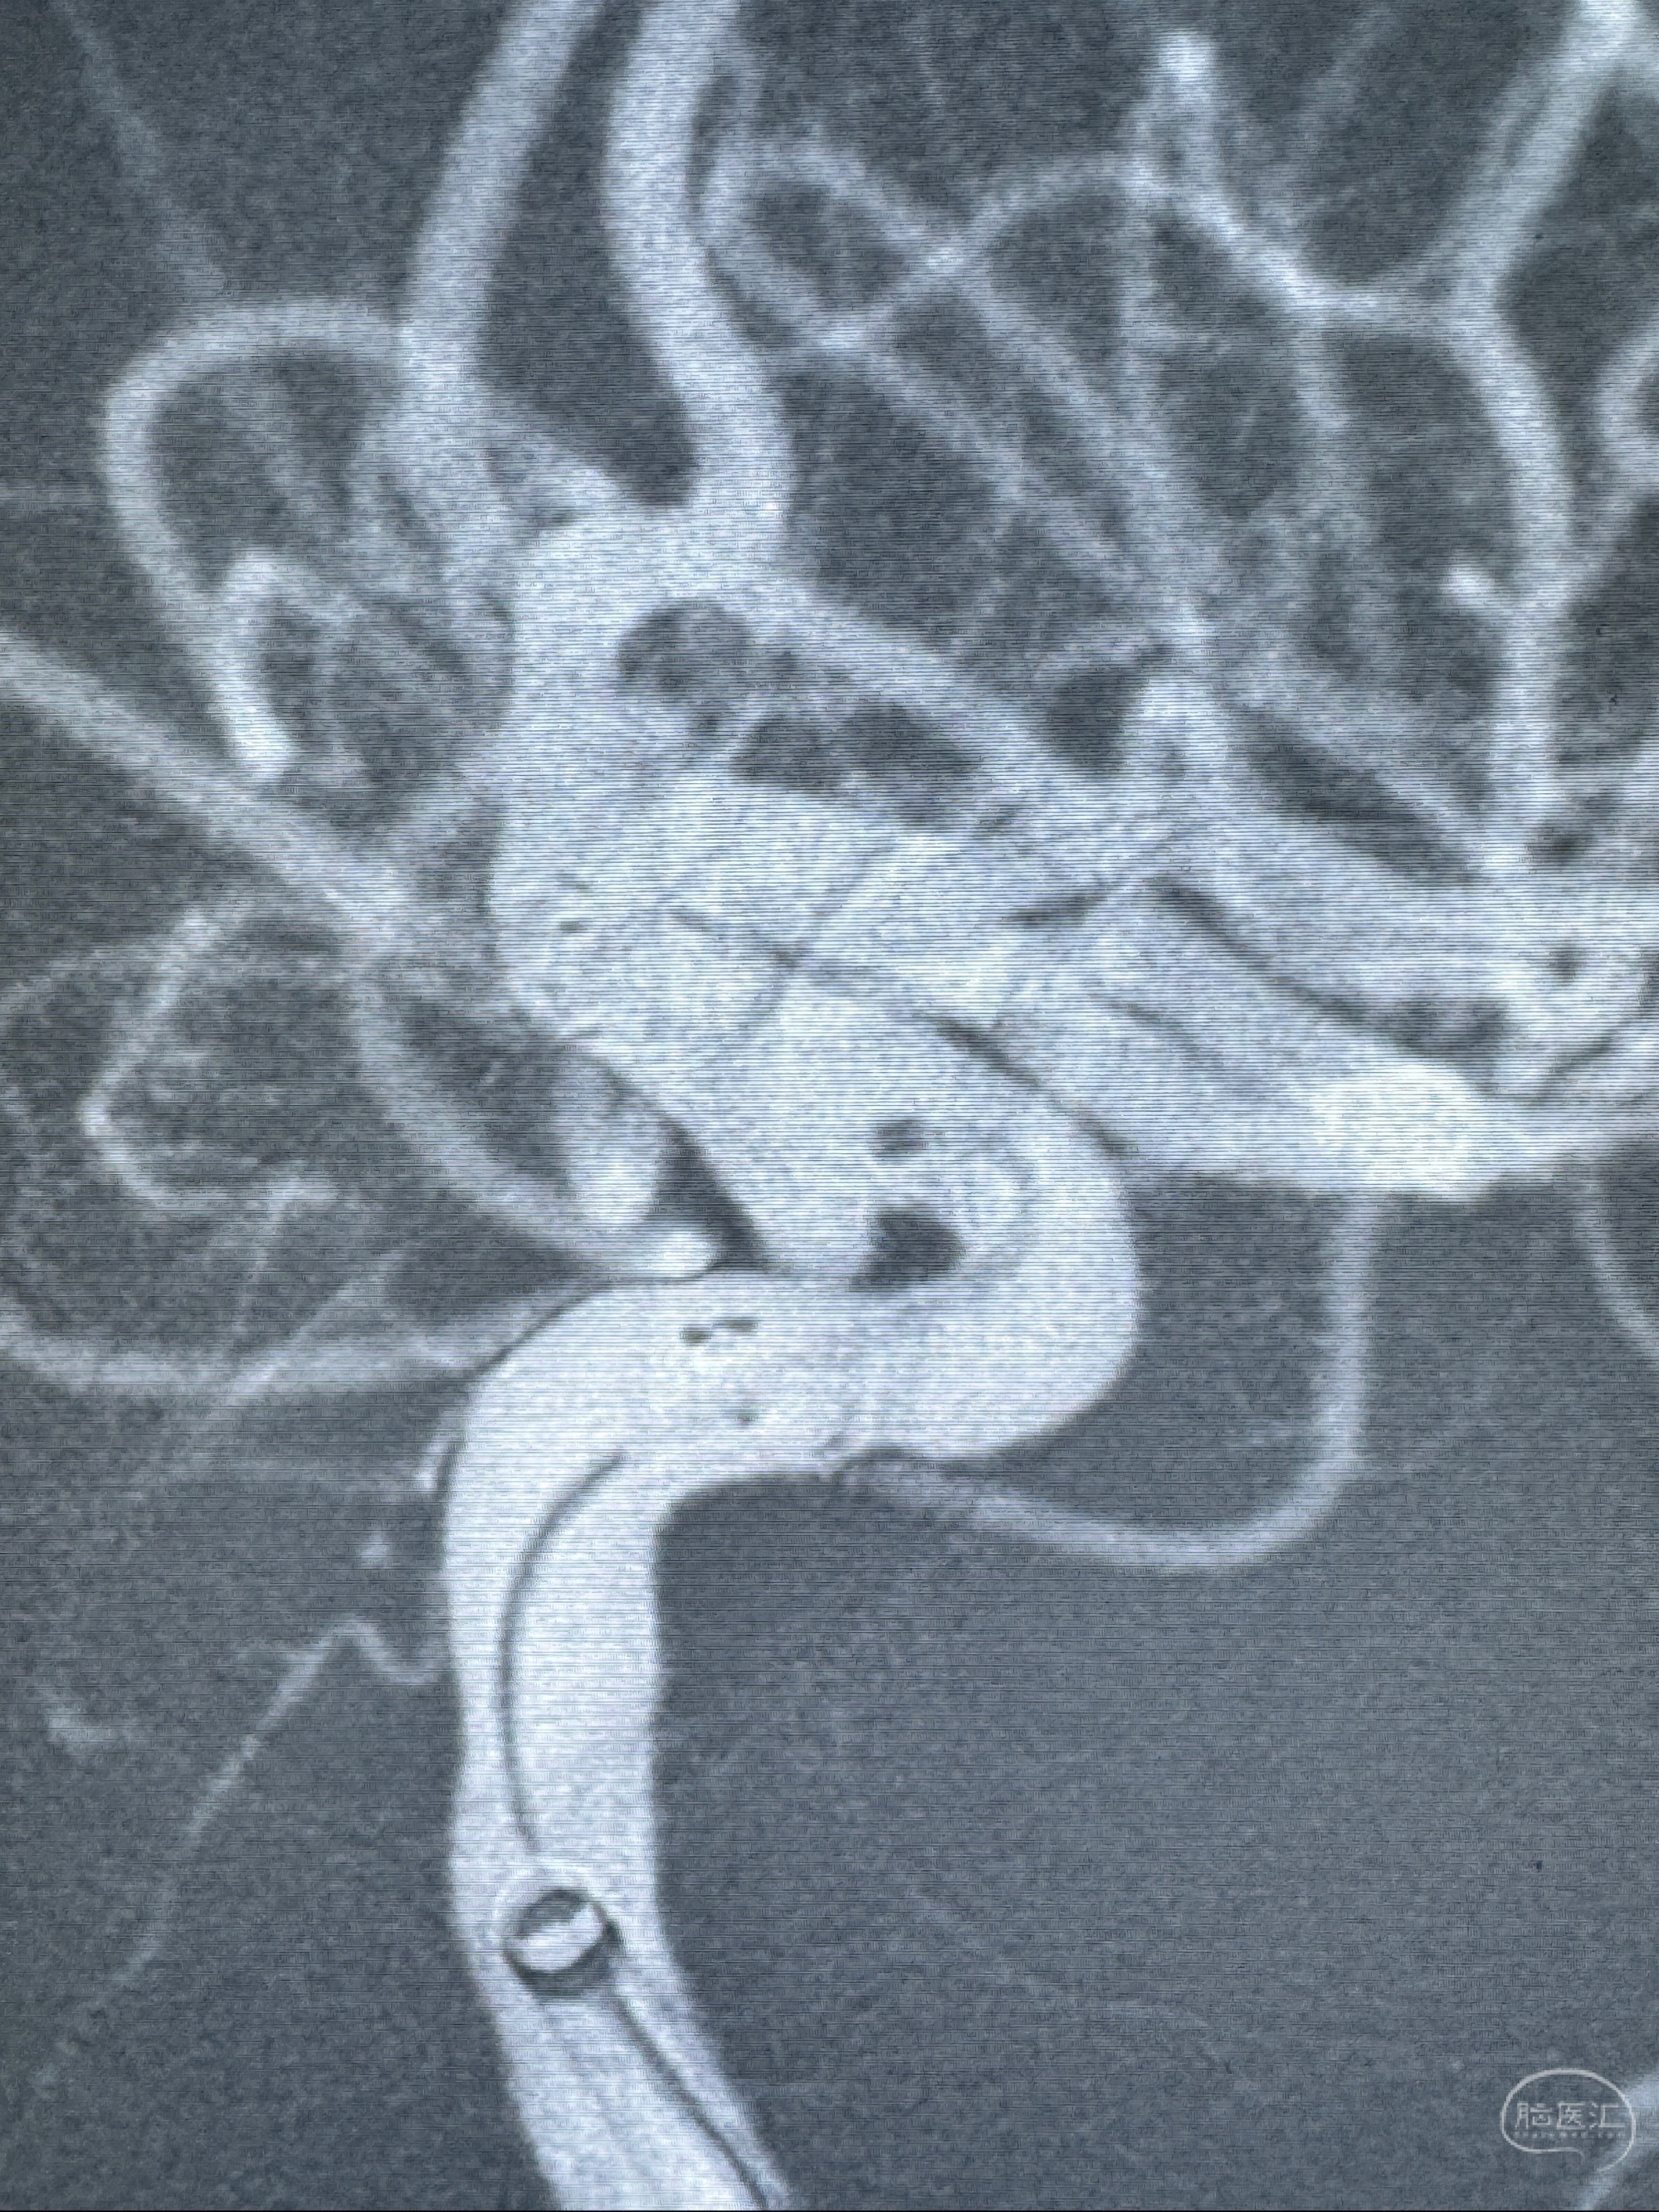

2023-11-13DSA:左侧颈内动脉眼动脉后壁动脉瘤

2023-11-29全麻下行NeuroformEZ4.5-20mm支架辅助栓塞

术后即刻CT